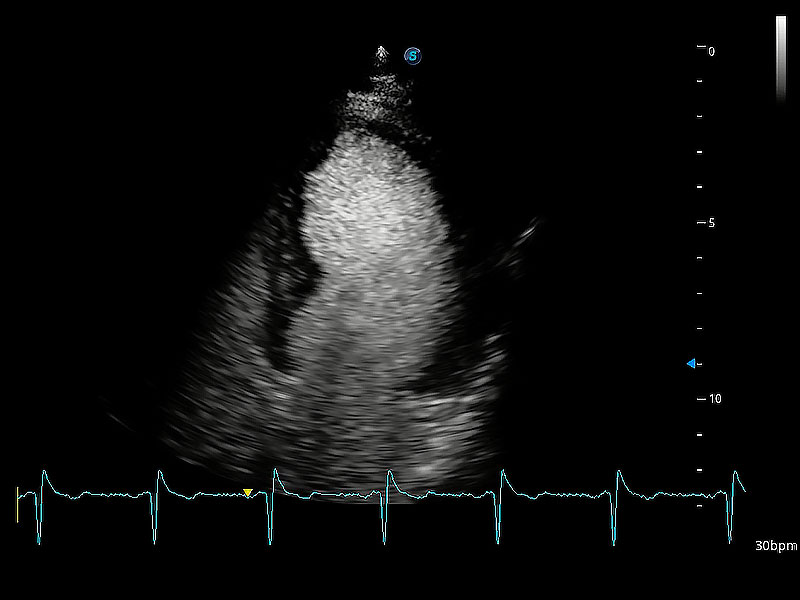

ProPet 80 配備了豐富的心臟探頭群、先進(jìn)的成像技術(shù)和專業(yè)的心臟測(cè)量工具,可幫助動(dòng)物醫(yī)生為不同體型和生理結(jié)構(gòu)的動(dòng)物提供心臟和心肌功能的全面評(píng)估。

能夠基于左心室壁追蹤和辛普森法,自動(dòng)計(jì)算射血分?jǐn)?shù),支持多個(gè)可移動(dòng)點(diǎn)描跡,與手動(dòng)測(cè)量相比,極大節(jié)省了動(dòng)物醫(yī)生的時(shí)間和精力。